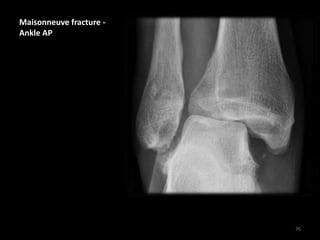

Maisonneuve fracture -

Ankle AP

• 1 - Disruption of the

medial ankle joint with

small bone avulsion

• 2 - Disruption of the

distal tibio-fibular

syndesmosis

• No fibular fracture is

visible at the ankle

raising the suspicion of

a proximal fibular

fracture